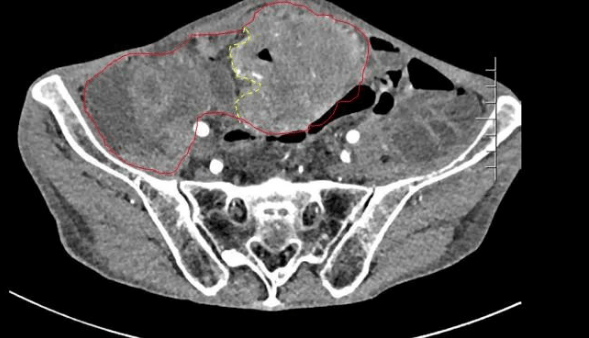

患者王大爺,男,72歲,發(fā)現(xiàn)腹腔腫物10余年,近兩年來患者雙下肢乏力、貧血,依靠間斷輸血維持著正常生活,出現(xiàn)頭昏,行動困難,腹部疼痛及便血慕名來我院就診。入院后查體評估患者年齡大,體質(zhì)差,嚴重貧血,肺部感染及腸梗阻征象,腹部增強CT檢查提示腹膜后巨大腫瘤,長徑超過30厘米,占據(jù)大部分腹腔,并可能存在雙原發(fā)腫瘤。

苗滿園腫瘤外科團隊在麻醉科/手術室的緊密配合下為該患者進行手術,術中發(fā)現(xiàn)腫瘤巨大,幾乎占據(jù)了整個腹腔,從左側(cè)向右腹腔延伸,向上將肝、腎擠向膈下,向左將胃及小腸擠向左上腹,向下深達盆腔內(nèi),包繞下腔靜脈、腸系膜上動脈等大血管及輸尿管,回盲部及回腸也受侵犯。手術難度巨大,風險極高。團隊憑借著高超的手術技能和精準的手術預案沉著應對,迎難而上,應用高頻電刀、超聲刀、切割縫合器等先進設備,耗時近5小時為患者切除了巨大腹腔腫瘤,并聯(lián)合右半結(jié)腸切除,術中出血僅50ml。術后病理為腹膜后巨大平滑肌瘤+回腸腺癌。